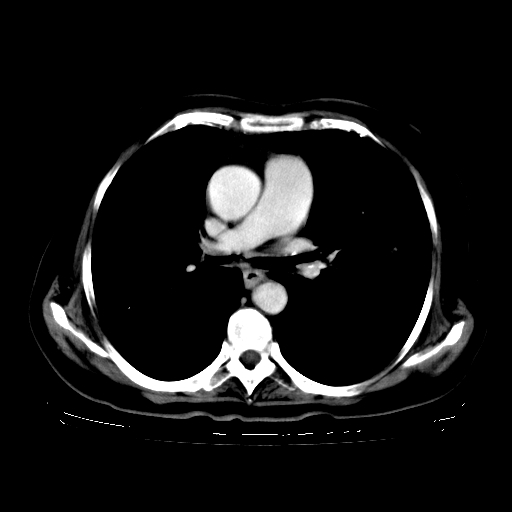

女,70岁,咳嗽、咳痰一个月,低热一周。

1.左上肺结核,部分纤维化。右肺中下叶部分肺不张,内见液化、坏死及点状钙化,右中下叶支气管壁增厚、管腔狭窄,见多个点状钙化,结合临床考虑支气管内膜结核,建议痰检查抗酸杆菌并参考血沉。两肺多个小圆点状高密度灶,境界模糊,多考虑结核肺内播散。但本人年龄较大首先应支气管镜检以除外右肺癌。

2.胸主动脉夹层。

支持,首先一元论解释。胸主动脉部分层面环形低密度,中心强化。环形影不强化。不象真假腔的改变。我考虑动脉炎,不太支持夹层动脉瘤-和大家的观点不一致,希望楼主让患者再做个心血管的彩超吧。